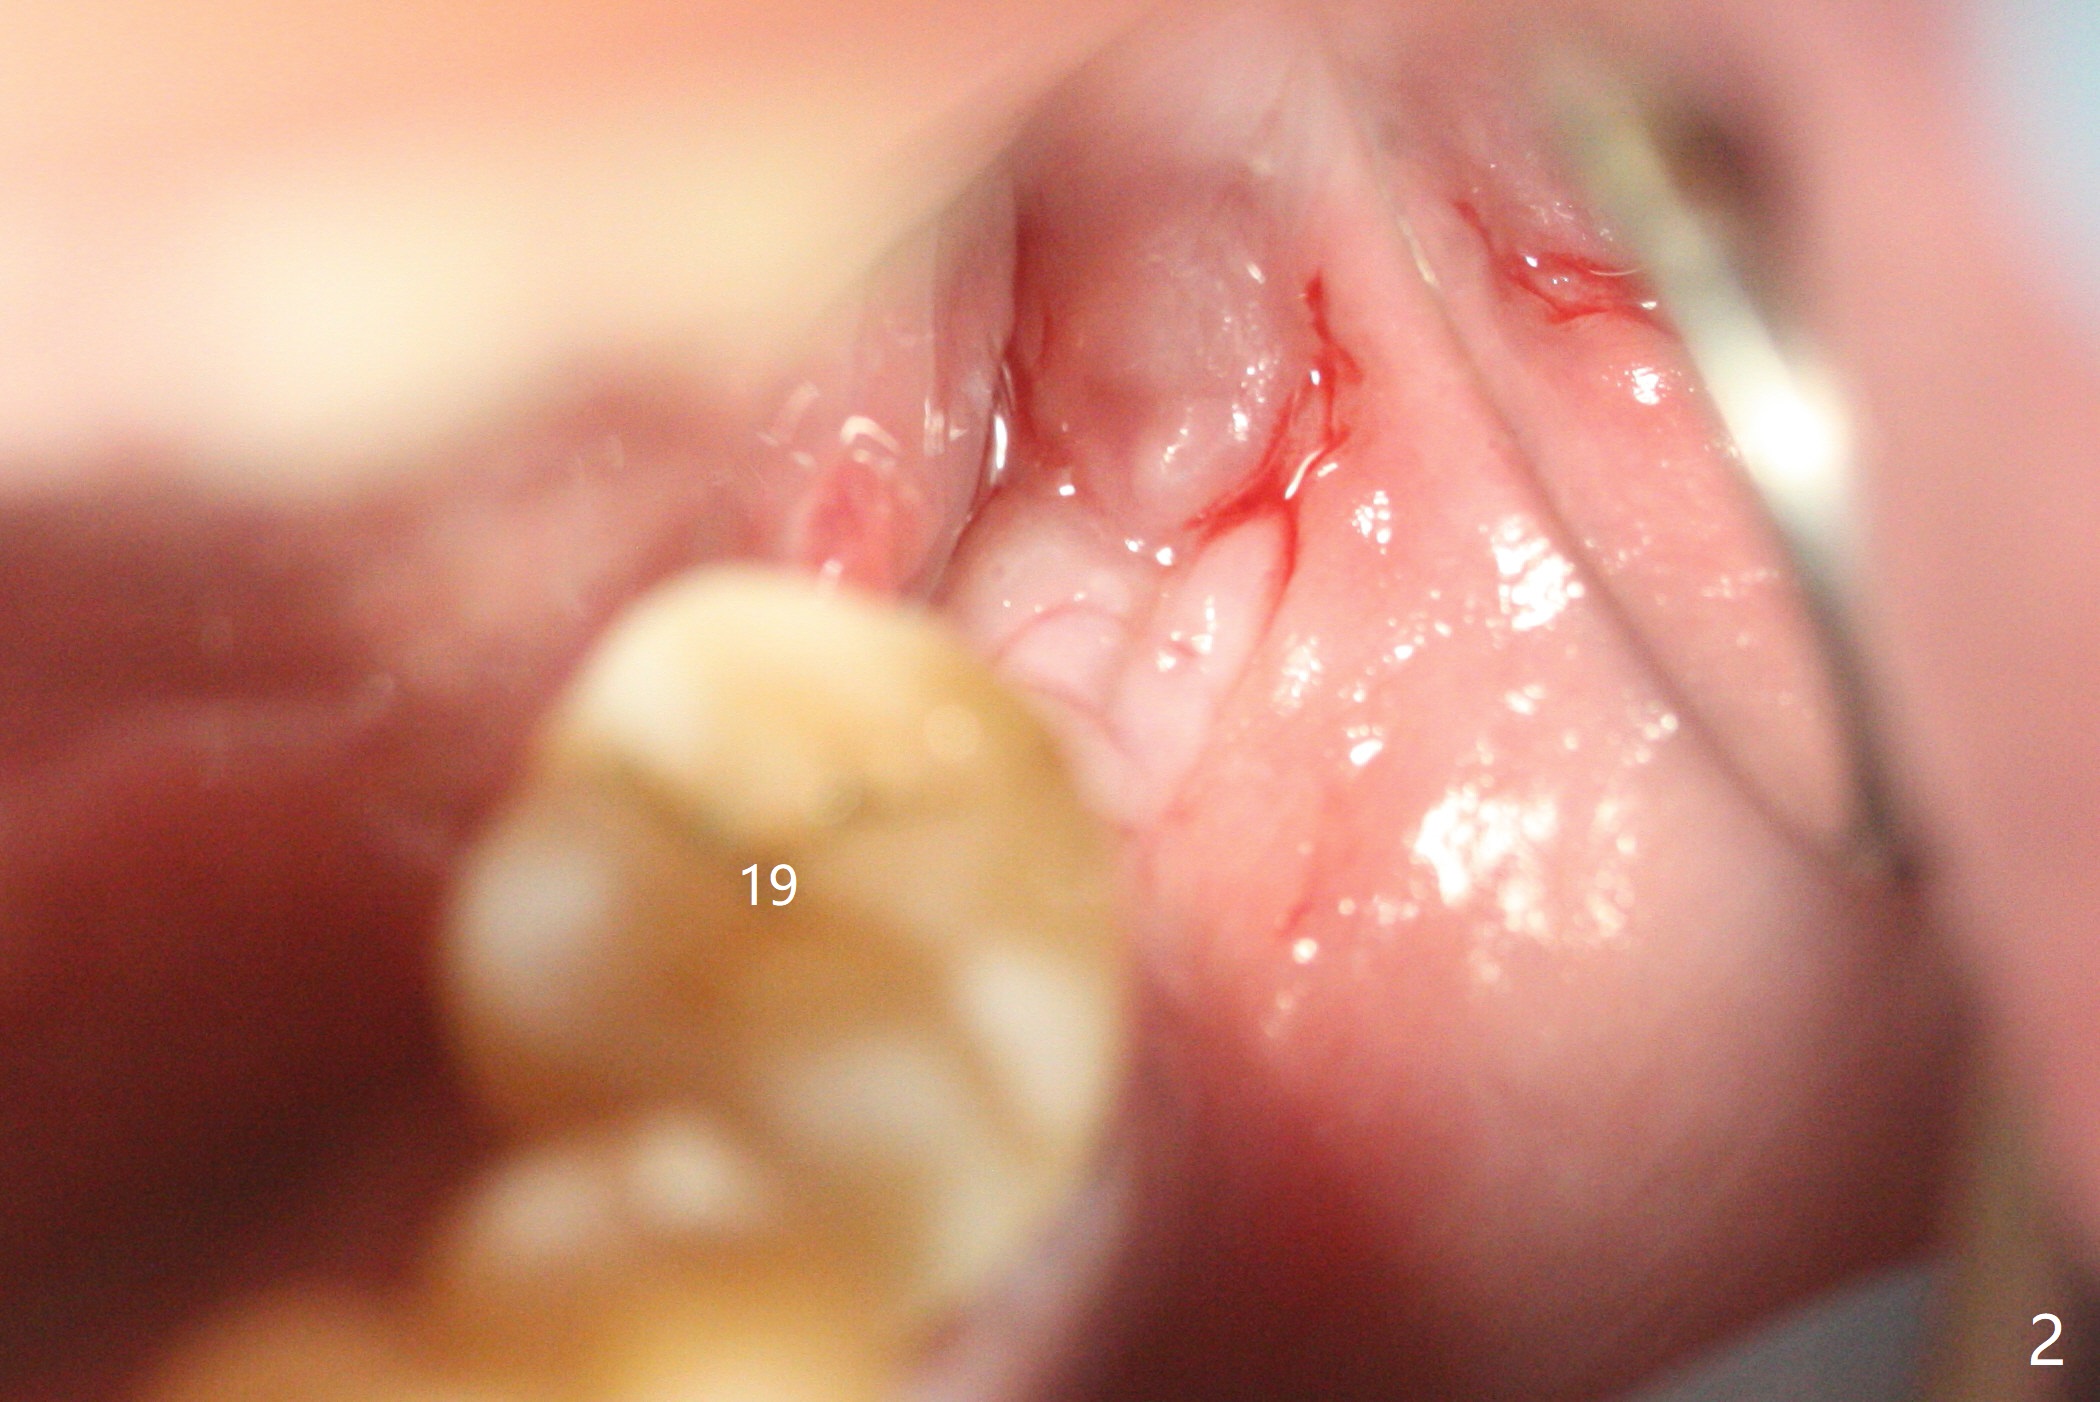

导板种植是否需要切开取决于牙槽嵴角化龈宽度,放置导板后,插入环形刀(图一),用手的压力(不要开手机)接触牙龈后,抽出环形刀,并且取出导板,检查环形标记是否累及颊侧粘膜(图二)。这个病例没有,所以没有切开,也没有保留角化龈(骨质硬,预计术后可以使用愈合基台)。在34毫克利多卡因17微克肾上腺素浸润(jinrun)麻醉下,完成钻洞(最后钻头3.5x10毫米),植体植入,拍摄CT却发现植体非常接近神经(图三,五),似乎钻洞向舌侧偏移(与设计(图四)对比),可能与没有远中牙齿固位有关。由于术中没有疼痛,估计没有直接损伤神经,放置愈合基台,在后者周围空间塞入骨粉(图六:*)。理想情景使用2.2x7.3毫米钻头后,拍摄CT,最后植入4.5或者5.0x7.3毫米植体(图五')。术后没有疼痛也没有麻木。